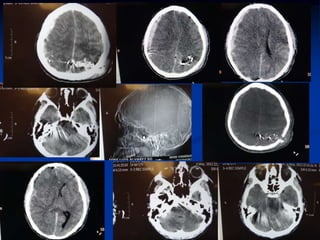

Contusion hemorragica

NO SE OPERA

Contusion cerebral son hemorragias parenquimaosas que

resulta de rosamiento y magullamiento del cerebro sobre las

partes salientes del craneo.

Se presenta en los lobulos frontal y temporal.. Se presentan

laceraciones.

CONTUSION CEREBRAL

NO CONMOCION CEREBRAL

Hematoma subdural

El origen es de sangre venosa entre la aracnoides y

la duramadre.

 Es originado por movimientos del cerebro dentro

del craneo que conduce un estiramiento y

desgarramiento de las venas que drenan de la

superficie del cerebro a los senos durales, o ruptura

de arterias piales.

Hemorragia Subaracnoidea

Es la extravasacion de sangre al espacio subaracnoideo a

consecuencia de l TCE

Se puede identificar realizando una PL ( no se hace)

Por TAC se observa la sangre en la convexidad a diferencia de

la ruptura de aneurisma en donde se ve la sangre en las

cisternas.

Las complicaciones como Hidrocefalia e isquemia son poco

frecuentes